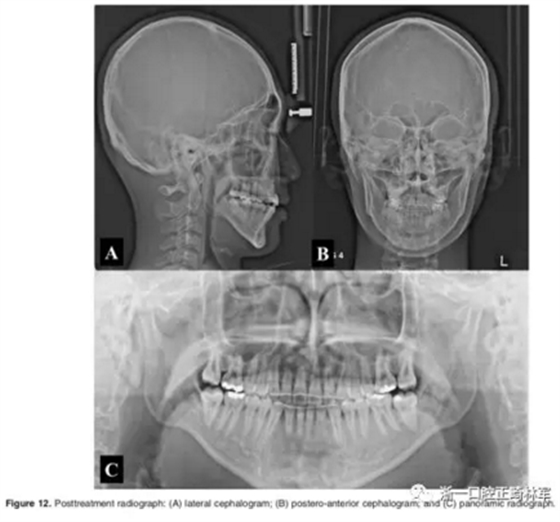

影像學(xué):頭顱側(cè)位片示:矢狀向和垂直向骨骼發(fā)生變化(ANB角,3°;SN-MP,51°);上頜切牙略前傾(U1-SN,106°),與下頜切牙一致(IMPA,75°);病人的面部輪廓得以保持。全景片示:由于牙齒萌出,上前牙區(qū)垂直向牙槽骨水平增加;雖然前牙牙根較彎曲,但其平行度仍可,且無明顯的牙根吸收。CBCT示:前牙唇側(cè)骨質(zhì)連續(xù)性改善,牙根唇側(cè)支持組織變好,牙槽骨高度、厚度均有增加,但轉(zhuǎn)矩的改變一定程度上導(dǎo)致了局部應(yīng)力的增大。